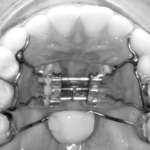

Benefici correlati all’utilizzo del flusso digitale nel trattamento della disgiunzione palatale Premium

La procedura standard per il posizionamento di un disgiuntore rapido palatale prevede una serie di appuntamenti scanditi nel tempo. Scopo di questo lavoro è stato quello di analizzare questi passaggi e sovrapporli a quelli utilizzati per il flusso digitale, valutando pro e contro dei due percorsi.